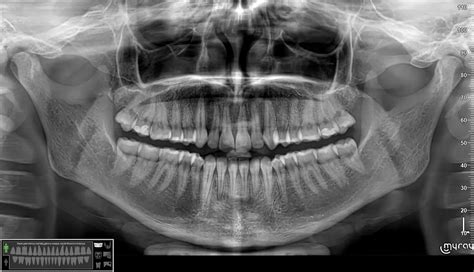

Tai, kaip reikėtų elgtis ir kokį gydymą taikyti patyrus danties traumą, priklauso nuo jos pobūdžio. Odontologas nedelsdamas suteiks informaciją, ką daryti konkrečios dantų traumos atveju. Dantų traumos gydomos atliekant įvairias odontologines ar chirurgines procedūras. Jų parinkimas priklauso nuo traumos tipo, todėl pirmiausia itin svarbi traumos diagnostika. Jai dažnai pasitelkiamos dantų rentgeno nuotraukos, gali būti atliekami papildomi tyrimai. Gydytojas padarys kelių krypčių rentgeno nuotraukas ir net priešingo žandikaulio dantų rentgeno nuotraukas, kad įvertintų, ar neįvyko šaknies lūžis. Dažnai padarius rentgeno nuotraukas, išaiškėja, kad dantų trauma sudėtingesnė, nei pasirodė iš pirmo žvilgsnio.